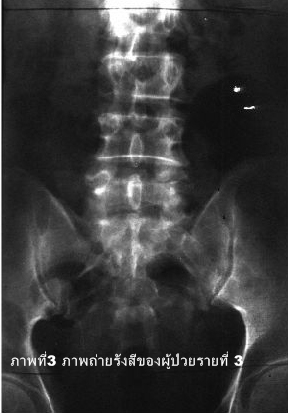

รายที่ 3

ชายอายุ 70 ปี รายงานว่าปวดหลังมากมานาน 2 เดือน. 1 เดือนก่อนมาโรงพยาบาลอาการปวด มากขึ้นโดยเฉพาะเวลากลางคืน. การตรวจภาพถ่ายทางรังสีปรากฏผลดังภาพที่ 3.

คำถาม

1. การตรวจที่เห็นคืออะไร.

2. บอกความผิดปกติที่เห็น.

3. จงให้การวินิจฉัยโรค.

4. จงให้การวินิจฉัยแยกโรค.

1. Plain film KUB.

2. พยาธิสภาพชนิดย่อยสลาย (lytic) บริเวณส่วน pedicle ของกระดูกสันหลังระดับ L5 ด้านซ้าย.

3. มะเร็งแพร่กระจายมายังส่วน pedicle ของกระดูกสันหลังระดับ L5 ด้านซ้าย.

4. การติดเชื้อเช่นวัณโรคบริเวณดังกล่าว โดยอาการทางคลินิกมักประกอบด้วยอาการไข้และปวดตลอดเวลา.